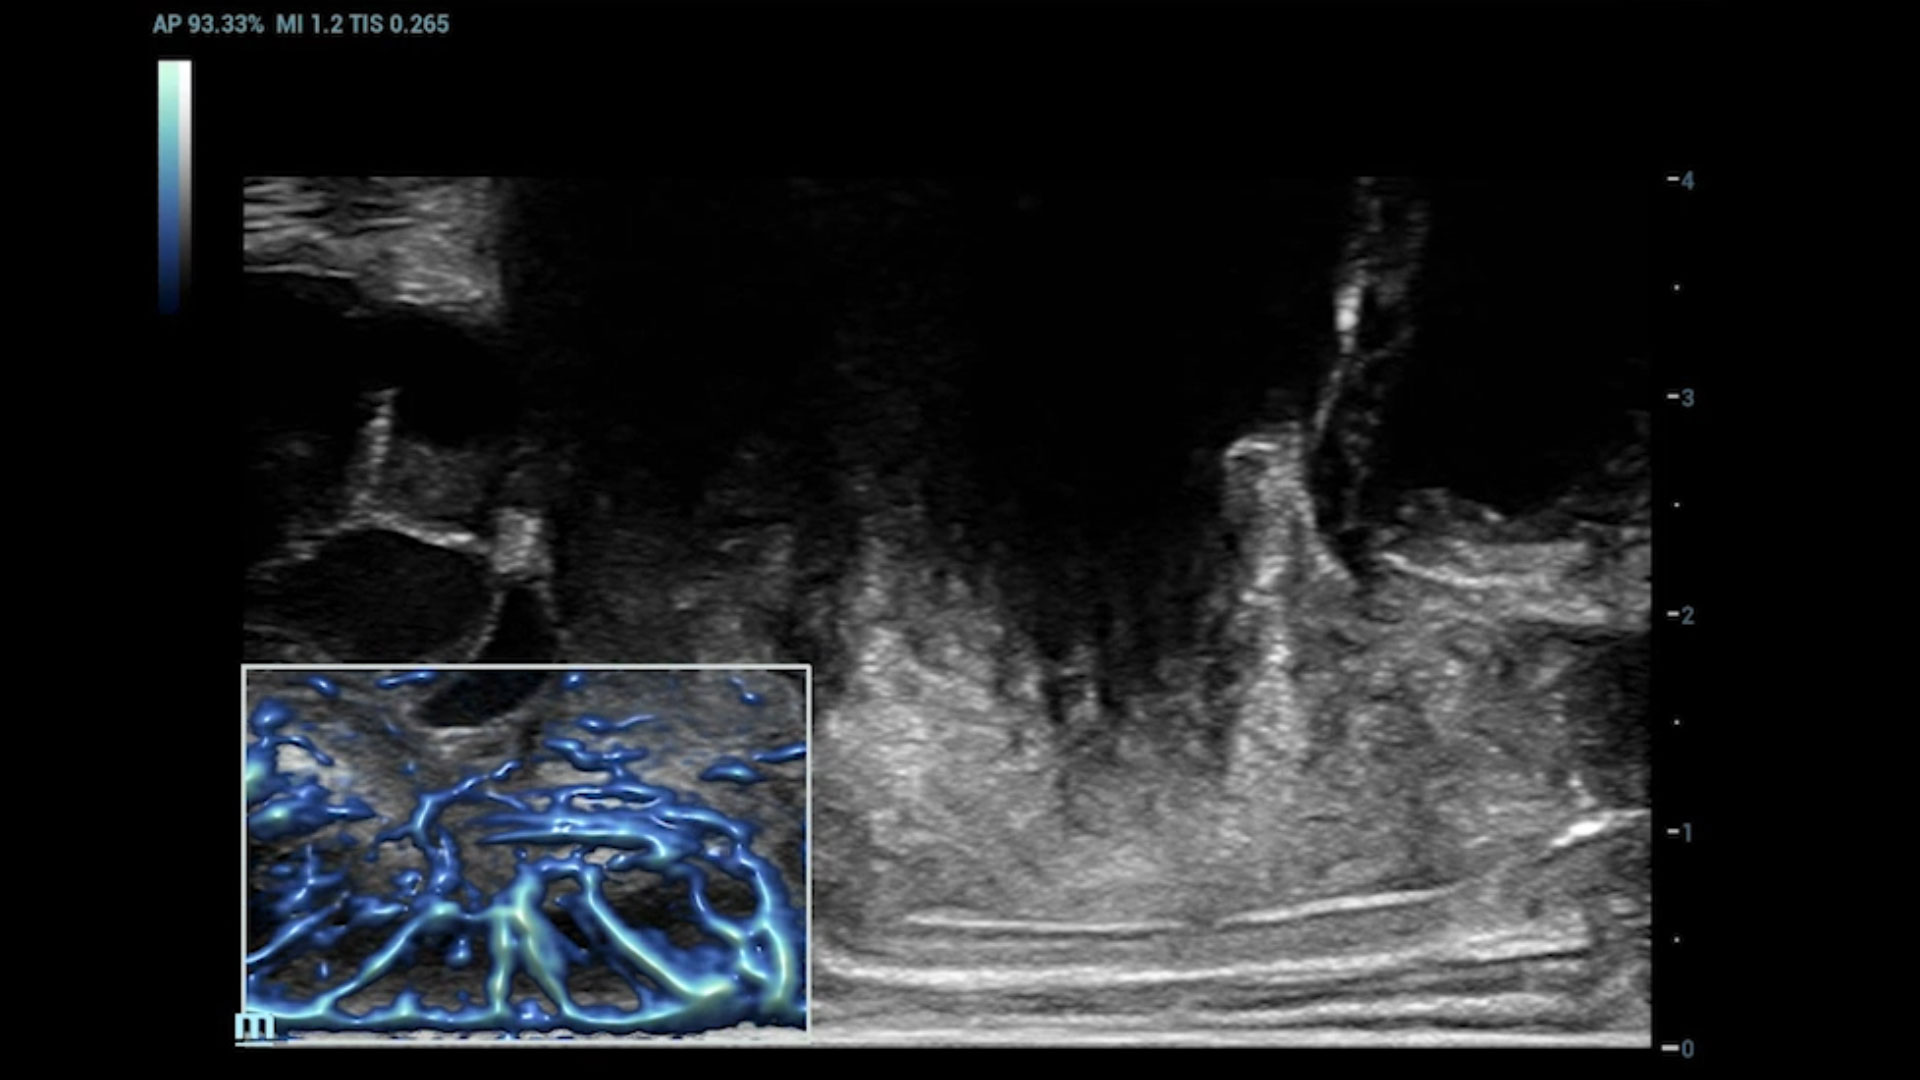

UMA (angiografia ultramicroscĆ³pica)

A tecnologia inovadora elimina as limita??es das tradicionais imagens com Doppler. Com resolu??o espacial e sensibilidade de fluxo ultra-altas, permite a detec??o de perfus?es de fluxos muito sutis e lentos, ampliando assim a aplica??o clĆnica da avalia??o qualitativa e quantitativa do ultrassom no cĆ©rebro fetal, rins, placentas, endomĆ©trios, ovĆ”rios etc.

UMA 3D ā Fluxo intracraniano do feto

UMA 3D ā Fluxo sanguĆneo perifolicular